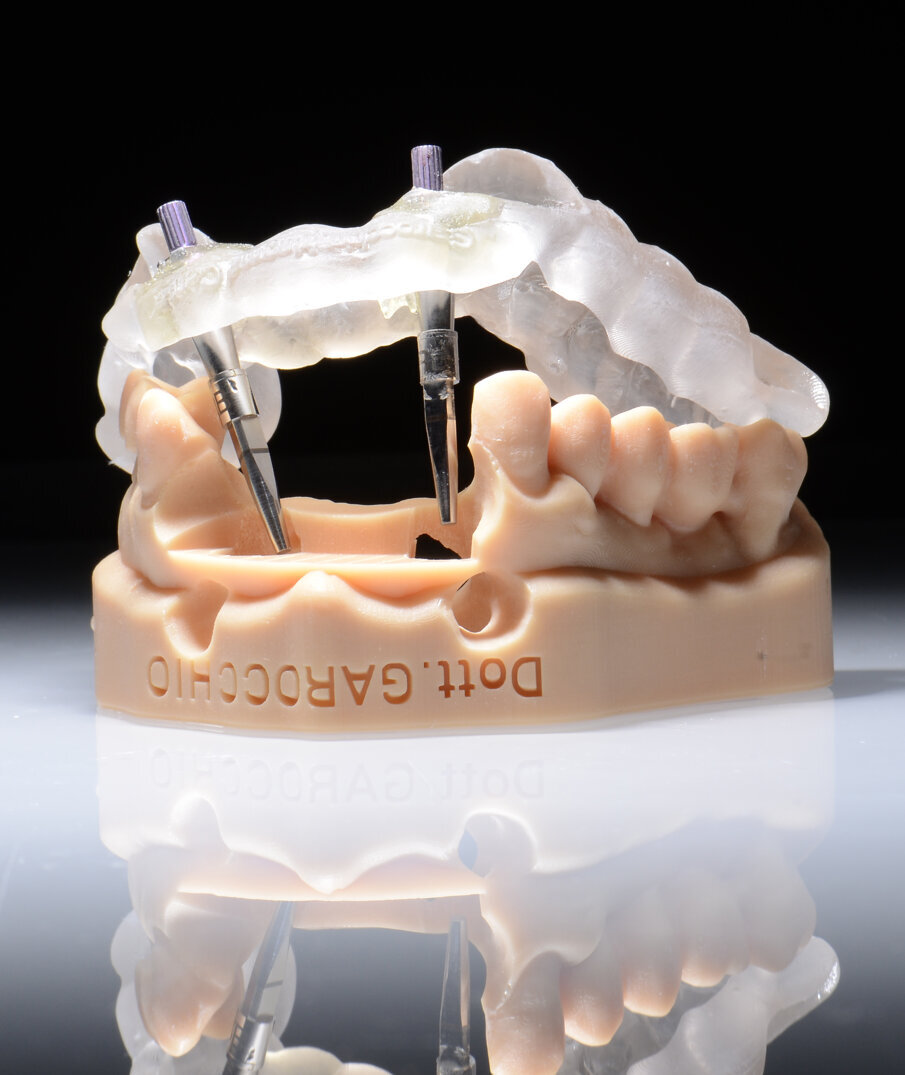

Dobbiamo quindi essere in grado, una volta definita la posizione corretta dell’impianto, di trasferire tutto clinicamente e di realizzare una fase chirurgica che possa rispettare tale programmazione. Voglio dunque ricavare dal progetto una dima chirurgica da utilizzare durante l’intervento: preparare il letto implantare e inserire l’impianto attraverso le guide consente di essere precisi e di realizzare l’intervento senza rischi. La dima chirurgica è realizzata attraverso stampanti 3D che oggi sono diventate molto affidabili. Le dime prodotte vengono controllate e posizionate su modelli stereolitografici ricavati dall’estrapolazione dei file STL direttamente da CoDiagnostiX, il software di chirurgia computer assistita di Dental Wings. La dima chirurgica adattata sul modello ci consente di verificarne, attraverso le finestre di ispezione, la congruità. Se la dima è precisa sul modello allora possiamo pensare di poter utilizzare lo stesso principio subito dopo il posizionamento implantare.

L’idea DIL (Digital Immediate Load) nasce da questa riflessione: se la dima viene alloggiata correttamente sul modello stereolitografico, e se la stessa viene utilizzata per inserire gli impianti allora possiamo pensare di utilizzare subito dopo il posizionamento implantare una seconda dima senza boccole (Sleeve) che chiameremo dima protesica. Subito dopo la chirurgia possiamo inserire attraverso gli spazi guidati i transfert da impronta sugli impianti e bloccarli con della resina alla dima stessa. In questo modo possiamo evitare di rilevare una nuova impronta (sia analogica che digitale) che ci costringerebbe a realizzare un nuovo modello e soprattutto a rilevare una nuova dimensione verticale specialmente nei casi di arcate edentule. Alla dima con i transfert bloccati vengono collegati gli analoghi. Questa unione tra dima protesica, transfert e analoghi degli impianti inseriti rappresenta il cuore della tecnica DIL. Infatti questo assemblato chirurgico-protesico viene riposizionato sul modello digitale master iniziale. Gli analoghi vengono a loro volta bloccati con della resina. Otteniamo così un modello master affidabile con la posizione corretta degli impianti (tecnica DIL). Questo tipo di approccio è stato in passato utilizzato con flussi analogici che avevano però un limite: il modello master ottenuto non era relazionabile all’antagonista e quindi si rendeva necessario un altro passaggio analogico per rilevare la nuova dimensione verticale8. Con la tecnica DIL, e quindi con un flusso tutto digitale il riposizionamento della dima protesica con i transfert sul modello master iniziale produrrà un modello master post chirurgico che avrà un duplice vantaggio, quello cioè di avere la posizione esatta degli impianti inseriti e quello di avere un’arcata già relazionata a quella antagonista (tecnica DIL). Sugli analoghi degli impianti, poi, vengono inserite le componenti secondarie scelte.

Il nostro obiettivo è quello di riuscire a dare alla paziente un provvisorio immediato nell’arco di due ore. Questo diventa possibile perché abbiamo utilizzato un flusso digitale fin dall’inizio. In laboratorio vengono realizzate la dima chirurgica (Figg. 16, 17), la dima protesica (Fig. 18) e anche il provvisorio (Figg. 19-21) che contiene delle alette di riposizionamento. Il tutto gestito con modelli digitali sui quali saremo in grado di funzionalizzare il provvisorio post-chirurgico (tecnica DIL). In un caso come questo se utilizziamo un flusso digitale possiamo evitare subito dopo la chirurgia di rilevare un’impronta degli impianti inseriti. Infatti, utilizziamo una dima chirurgica che ci faciliterà le fasi di intervento. La dima ci consentirà di non fare lembi e nessuna incisione di rilascio (Fig. 22), dopo aver inserito gli impianti (BLX Straumann) (Figg. 23-31) e aver controllato il loro alloggiamento, inseriamo sugli stessi dei transfert da impronta (Fig. 32).

Fig. 17 - Dima chirurgica.

Fig. 23- Posizionamento della dima.

Fig. 24 - Visione Occlusale.

Alloggiamo la dima protesica (Fig. 33), e blocchiamo i transfert con della resina trasparente (tecnica DIL) (Figg. 34, 35). In questo modo possiamo far riposare il paziente in studio dopo appena 35 minuti dall’inizio dell’intervento. La dima protesica, infatti (Fig. 36) con i transfert inseriti viene completata con l’unione degli analoghi ai transfert (Fig. 37). L’insieme così composto viene riadattato sul modello master digitale iniziale (Figg. 38-40) sul quale era stata costruita sia la dima chirurgica che la dima protesica come anche il provvisorio. Gli analoghi vengono bloccati sul modello con resina trasparente (Figg. 41-43). Alloggiamo il provvisorio sul modello master digitale così ottenuto (Figg. 44, 45).